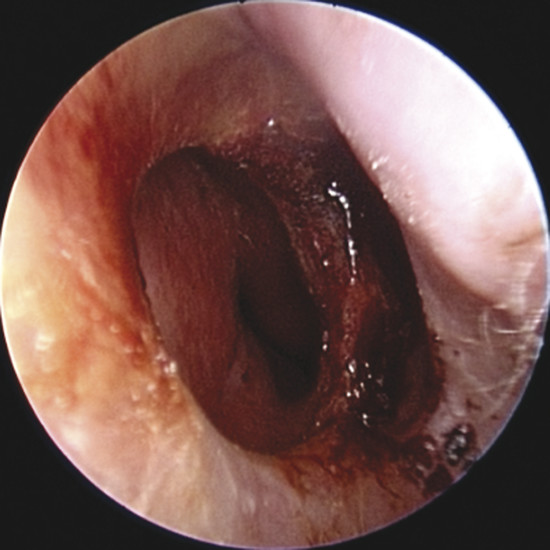

Upon physical examination of the nose, a full diagnosis cannot be made until all crusts have been removed and decongestion of the turbinates has taken place, making it possible to visualize the entire nasal septum. The nasal endoscopy allows appreciating the configuration of the NSP, the presence or absence of adherent crusts on the edges of the defect (Fig. 6‑1), any easily bleeding areas (Fig. 6‑2), and the state of the remaining mucosa, which may present some aspects regarding ischemic conditions (cocaine abuse) (Fig. 6‑3).